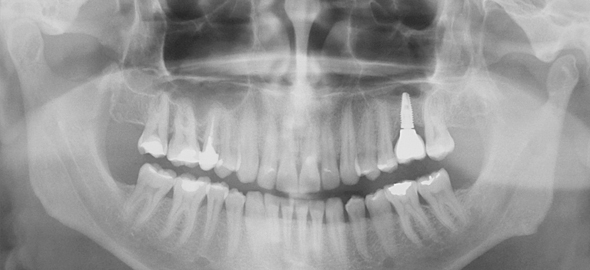

IMPLANTES

São parafusos de titânio que substituem dentes ausentes.

A implantodontia reabilita pacientes que, por algum motivo (cultural, financeiro ou por desmotivação), perderam seus dentes. Repõe dentes de pacientes que sofreram traumas ou que tem agenesias (ausência de dentes por motivos genéticos).

Este tratamento surgiu para substituir as próteses fixas e removíveis, as quais necessitam de desgastes dentários para serem realizadas.É um tratamento muito seguro e eficaz, tanto para substituir um ou todos os dentes, como nos casos de pacientes portadores de prótese total.

CARGA IMEDIATA

É uma técnica que consiste na instalação dos implantes e colocação de prótese no mesmo momento ou em até 72 horas.

Atualmente esta técnica pode ser aplicada para casos unitários ( apenas 1 dente) ou para casos de múltiplos dentes ( prótese protocolo)